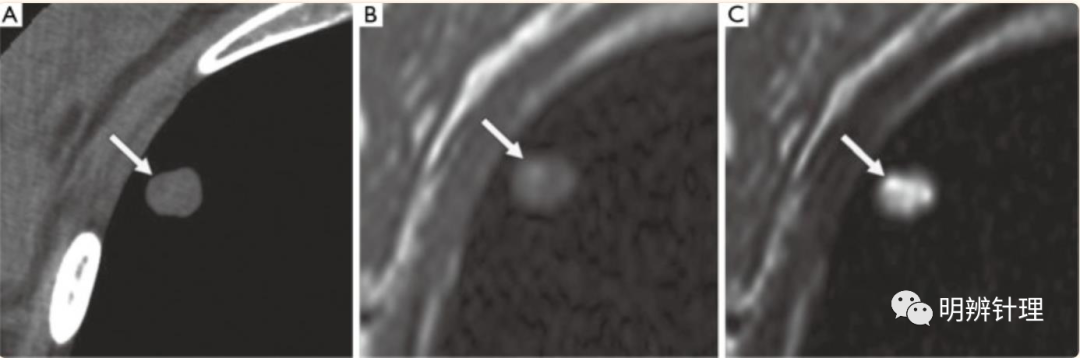

女性40 岁。(A) CT 图像显示结节内的低密度点(箭头),提示类脂组织;(B,C) 轴位 T1 加权 (B) 和 T2 加权 (C) MR 图像显示结节内的高信号点(箭头)。T2 加权图像 (C) 显示与软骨组织一致的超强度矩阵。

诊断结果:肺错构瘤